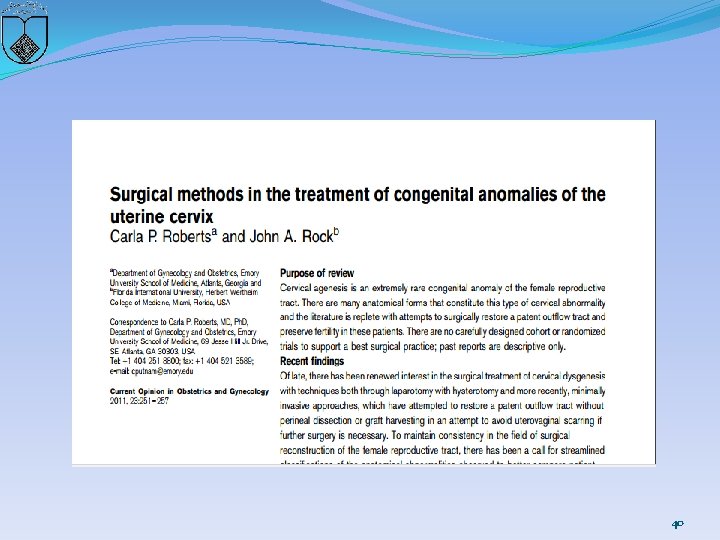

�Historically, the preferred treatment was hysterectomy, given this condition was not considered compatible with future fertility �less aggressive surgical procedures : �uses molds and both skin and "mucosal" grafts to create an upper vagina and cervical endocervical tract to allow menstruation and potentially enable spontaneous conception and successful pregnancy �disadvantages of this approach: risks of recurrent obstruction and ascending infection, which can lead to sepsis and death 34

recommended approach �The first step : defining the anatomy prior to performing any reconstructive procedure �cervix is a thin cord or the uterine cavity is hypoplastic �or absent, the uterus and cervical remnants are removed �If a reconstructive procedure is performed, epithelialization with a suitable graft of neocervical canal is recommended 41

uterovaginal anastomosis �complete dissection of the rectouterine and vesicouterine space to expose the vagina or neovaginal canal, �allowing circumferential anastomosis of the vagina and stroma to the lower uterine segment. The uterus is pulled down and sutured to the vagina or vestibular mucosa A stent (16 French Foleycatheter) is placed with or without a mold, depending on surgeon preference or the need to graft the newly createdneovagina. �The patient is given a broad-spectrum antibiotic for 15 days. 42

Key points � Hysterectomy is recommended for the patients with complete cervical agenesis. � High uterovaginal graft, at the line of the endometrium in the lower uterine segment, may produce a more successful uterovaginal anastomosis. There is a high risk of stenosis and fibrosis at the anastomosis site. � Cervicovaginal anastomosis may be accomplished in the patients with an endocervical canal. Cervicovaginal anastomosis and cervical grafting may be required. � When necessary, the surgeon should be prepared to perform a vaginoplasty, whether or not the uterus is preserved. � The anatomical findings in the cervix and patient preferences must be used for a comprehensive treatment strategy to afford the most successful outcome. � Complications following uterovaginal anastomosis are not insignificant and include endometritis, pelvic inflammatory disease, persistent pelvic pain, bowel and bladder injury, re-obstruction and stenosis requiring reoperation and death. 44